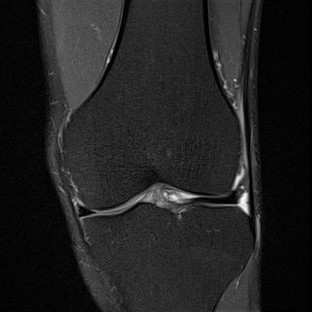

Limited by imaging systems, the reconstruction of Magnetic Resonance Imaging (MRI) images from partial measurement is essential to medical imaging research. Benefiting from the diverse and complementary information of multi-contrast MR images in different imaging modalities, multi-contrast Super-Resolution (SR) reconstruction is promising to yield SR images with higher quality. In the medical scenario, to fully visualize the lesion, radiologists are accustomed to zooming the MR images at arbitrary scales rather than using a fixed scale, as used by most MRI SR methods. In addition, existing multi-contrast MRI SR methods often require a fixed resolution for the reference image, which makes acquiring reference images difficult and imposes limitations on arbitrary scale SR tasks. To address these issues, we proposed an implicit neural representations based dual-arbitrary multi-contrast MRI super-resolution method, called Dual-ArbNet. First, we decouple the resolution of the target and reference images by a feature encoder, enabling the network to input target and reference images at arbitrary scales. Then, an implicit fusion decoder fuses the multi-contrast features and uses an Implicit Decoding Function~(IDF) to obtain the final MRI SR results. Furthermore, we introduce a curriculum learning strategy to train our network, which improves the generalization and performance of our Dual-ArbNet. Extensive experiments in two public MRI datasets demonstrate that our method outperforms state-of-the-art approaches under different scale factors and has great potential in clinical practice.